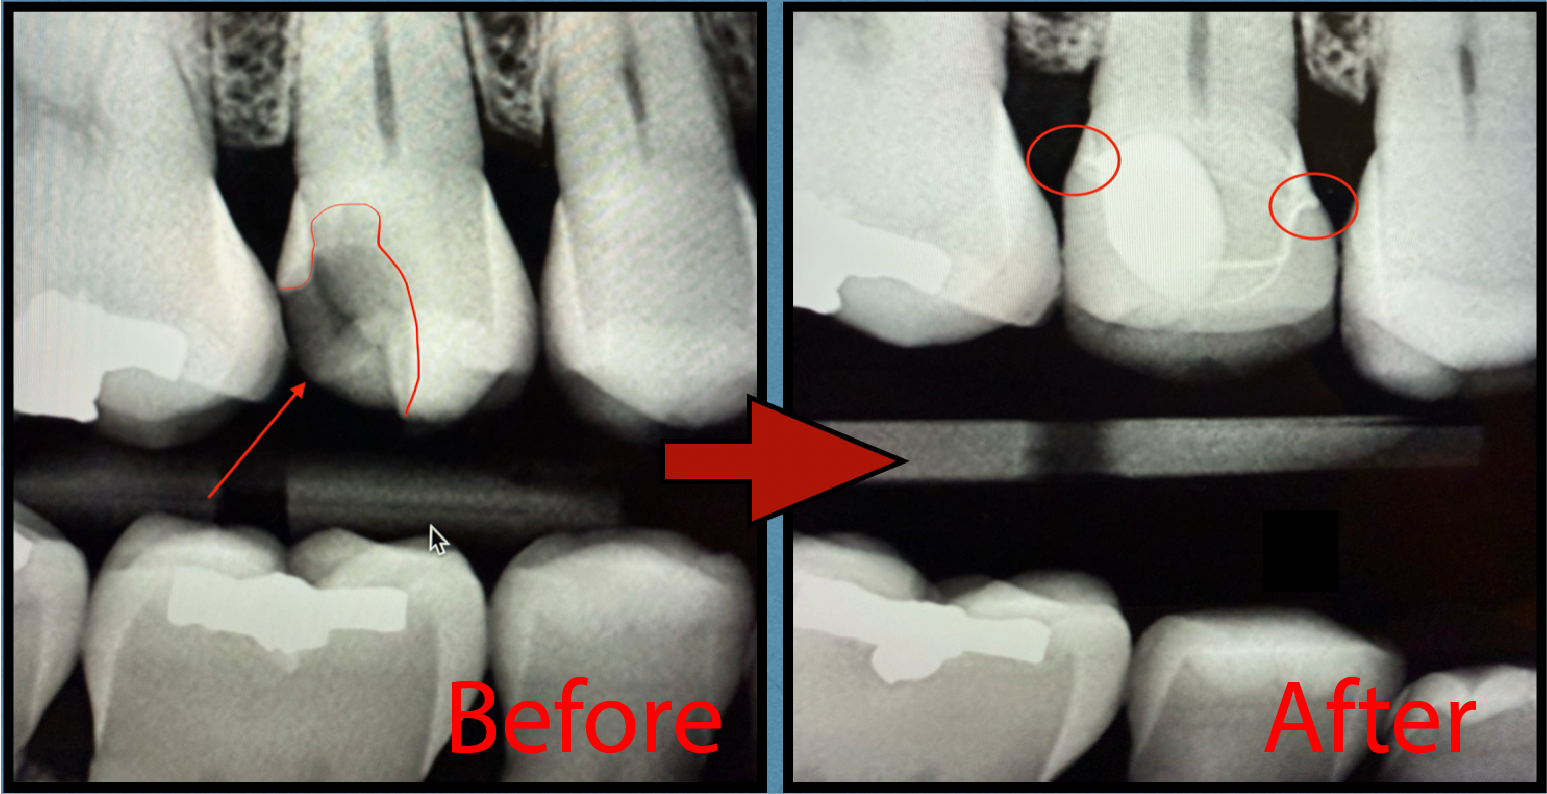

The images below show a perfect example:

- Before: An older crown looked intact on the surface, but x-rays revealed leakage around the margins. This allowed bacteria to slip underneath, leading to decay and ultimately loosening the crown.

- After: The tooth was rebuilt and restored with a new, custom crown. Notice how the new restoration forms a seamless, tight bond with the natural tooth. This strong seal not only restores appearance and function but also protects against future leakage and decay.